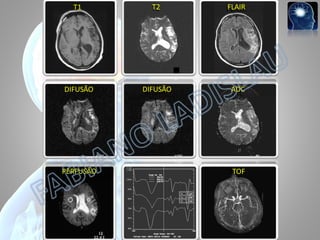

T1

T2

FLAIR

DIFUSÃO

ADC

PERFUSÃO

TOF